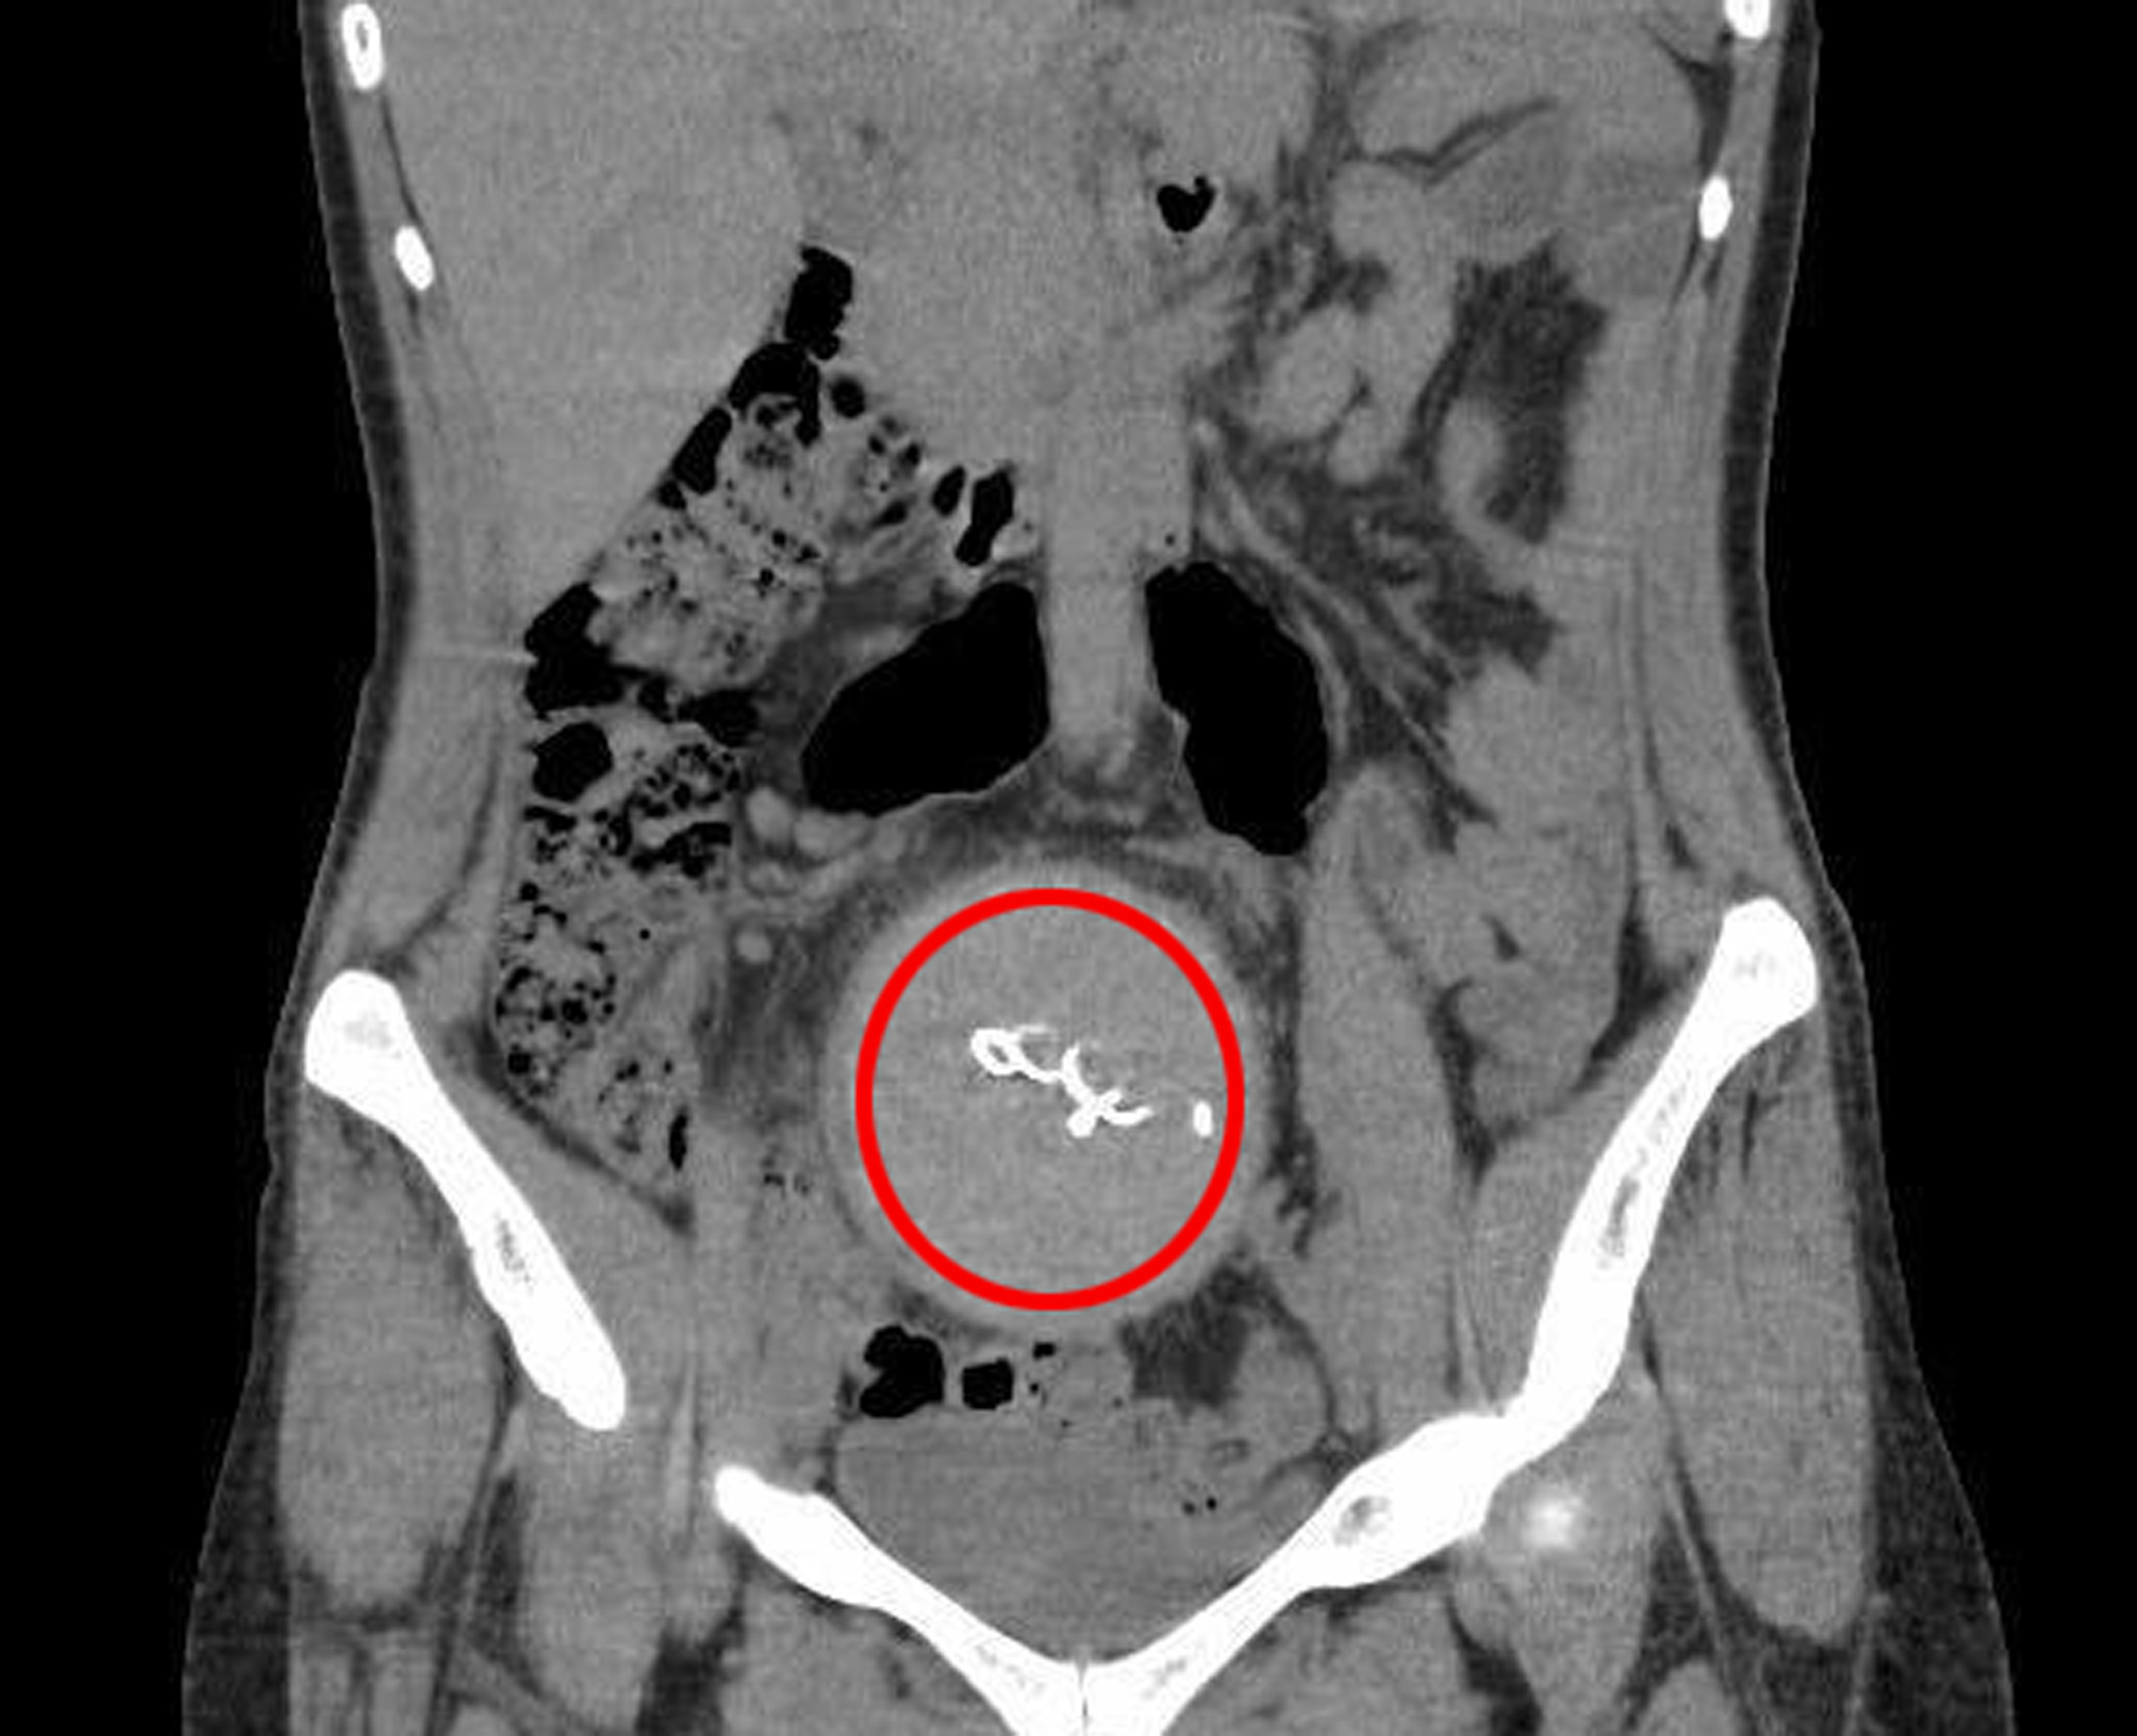

Burada yapılan kontrolde, doktor acil tomografi çektirmesini istedi. 2023 yılının Ağustos ayında çekilen tomografide, Y.S.'nin vücudunda doğum sonrası unutulan sargı bezi görüldü. Şoke olan Y.S., 2 yıldır yaşadığı ağrılara ihmalin sebep olduğunu öğrendi. Y.S.'nin karnında unutulan yaklaşık 30 santimetre uzunluğundaki gazlı bez ameliyatla alındı. Y.S., hastane ve süreç içerisinde ihmali bulunan doktorlar hakkında savcılığa suç duyurusunda bulundu.

Doktor E.B. ifadesinin devamında şöyle dedi: "İnceleme alanıma girdiği kadarıyla batındaki bağırsak anslarında ileri derecede distansiyon (karın şişliği) olduğundan bahsedilmiştir. Yapılan ikinci gözlemde de bağırsaklarda geçiş tıkanıklığı tanısı konulmuştur. Benim gerçekleştirdiğim işlemde herhangi bir eksik ve atlama yoktur. Aksine Gossypiboma (hastanın vücudunda yabancı cisim unutulması) varlığında erken dönemde görülebilecek en olası patolojik durum olan tıkanıklık tanısı konulmuştur. Bundan sonrası klinisyenin değerlendirmesiyle sonuçlandırılabilecek bir süreçtir. Kullanılan gazlı bezin radyopak madde ile işaretli olmaması da tanısal gecikmede rol oynamıştır."